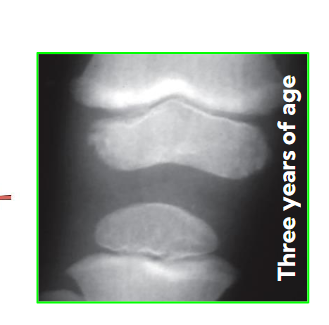

When do bones start developing and for how long?

They start as clusters of cells and then develop into bones

They start developing at the 6 WEEK GESTATION period and continue to develop until 20 years of age.

What happens to the bone at the before “birth” part of the timeline?

The bone starts to form a blood supply to the main shaft

As this happens, bone starts to develop in this area with helps it grow

What happens during the “birth” phase of the timeline (second ossification center)?

Main part of the bone is growing as well as the secondary site of the bone

Epiphyseal plates

A separation between the main part and secondary part of the bone

Literally means “Outside of growth” : Growth outside of the original bone

These close and create epiphyseal lines